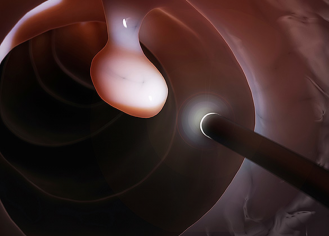

Осложнения при полипэктомии

Не удаление полипов (если к этому есть показания) может привести к более серьезным последствиям и осложнениям — колоректальному раку. А вот тут вы уже готовы будете на операцию, да только может быть поздно. Я не собираюсь вас пугать, а предлагаю обсудить какие же ОСЛОЖНЕНИЯ могут быть при ПОЛИПЭКТОМИИ: Согласно различным научным источникам, частота встречаемости кровотечения после полипэктомии — 0,09-1,1%

перфорации — 0,03-0,6%

Как видите, процент осложнений низкий. Для того, чтобы снизить риски осложнений после полипэктомии, необходимо соблюдать рекомендации вашего врача по физ.активности и питанию.